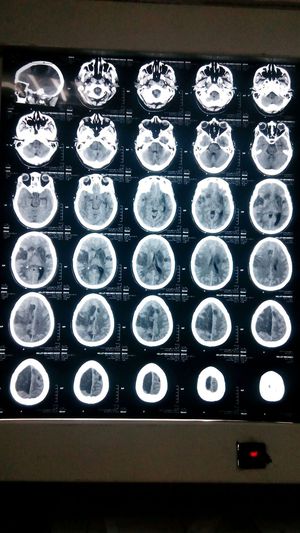

This 45 year old female experienced hypoperfusion during a minimally invasive mitral valve replacement surgery The patient showed delayed recovery upon admission to icu, first ct brain showed no abnormalities, however the patient didn't regain full consciousness. The follow up ct brain (shown above) showed multiple brain infarctions in both hemispheres

Double antiplatelets(aspirin, clopidogrel). And no, she didn't recover